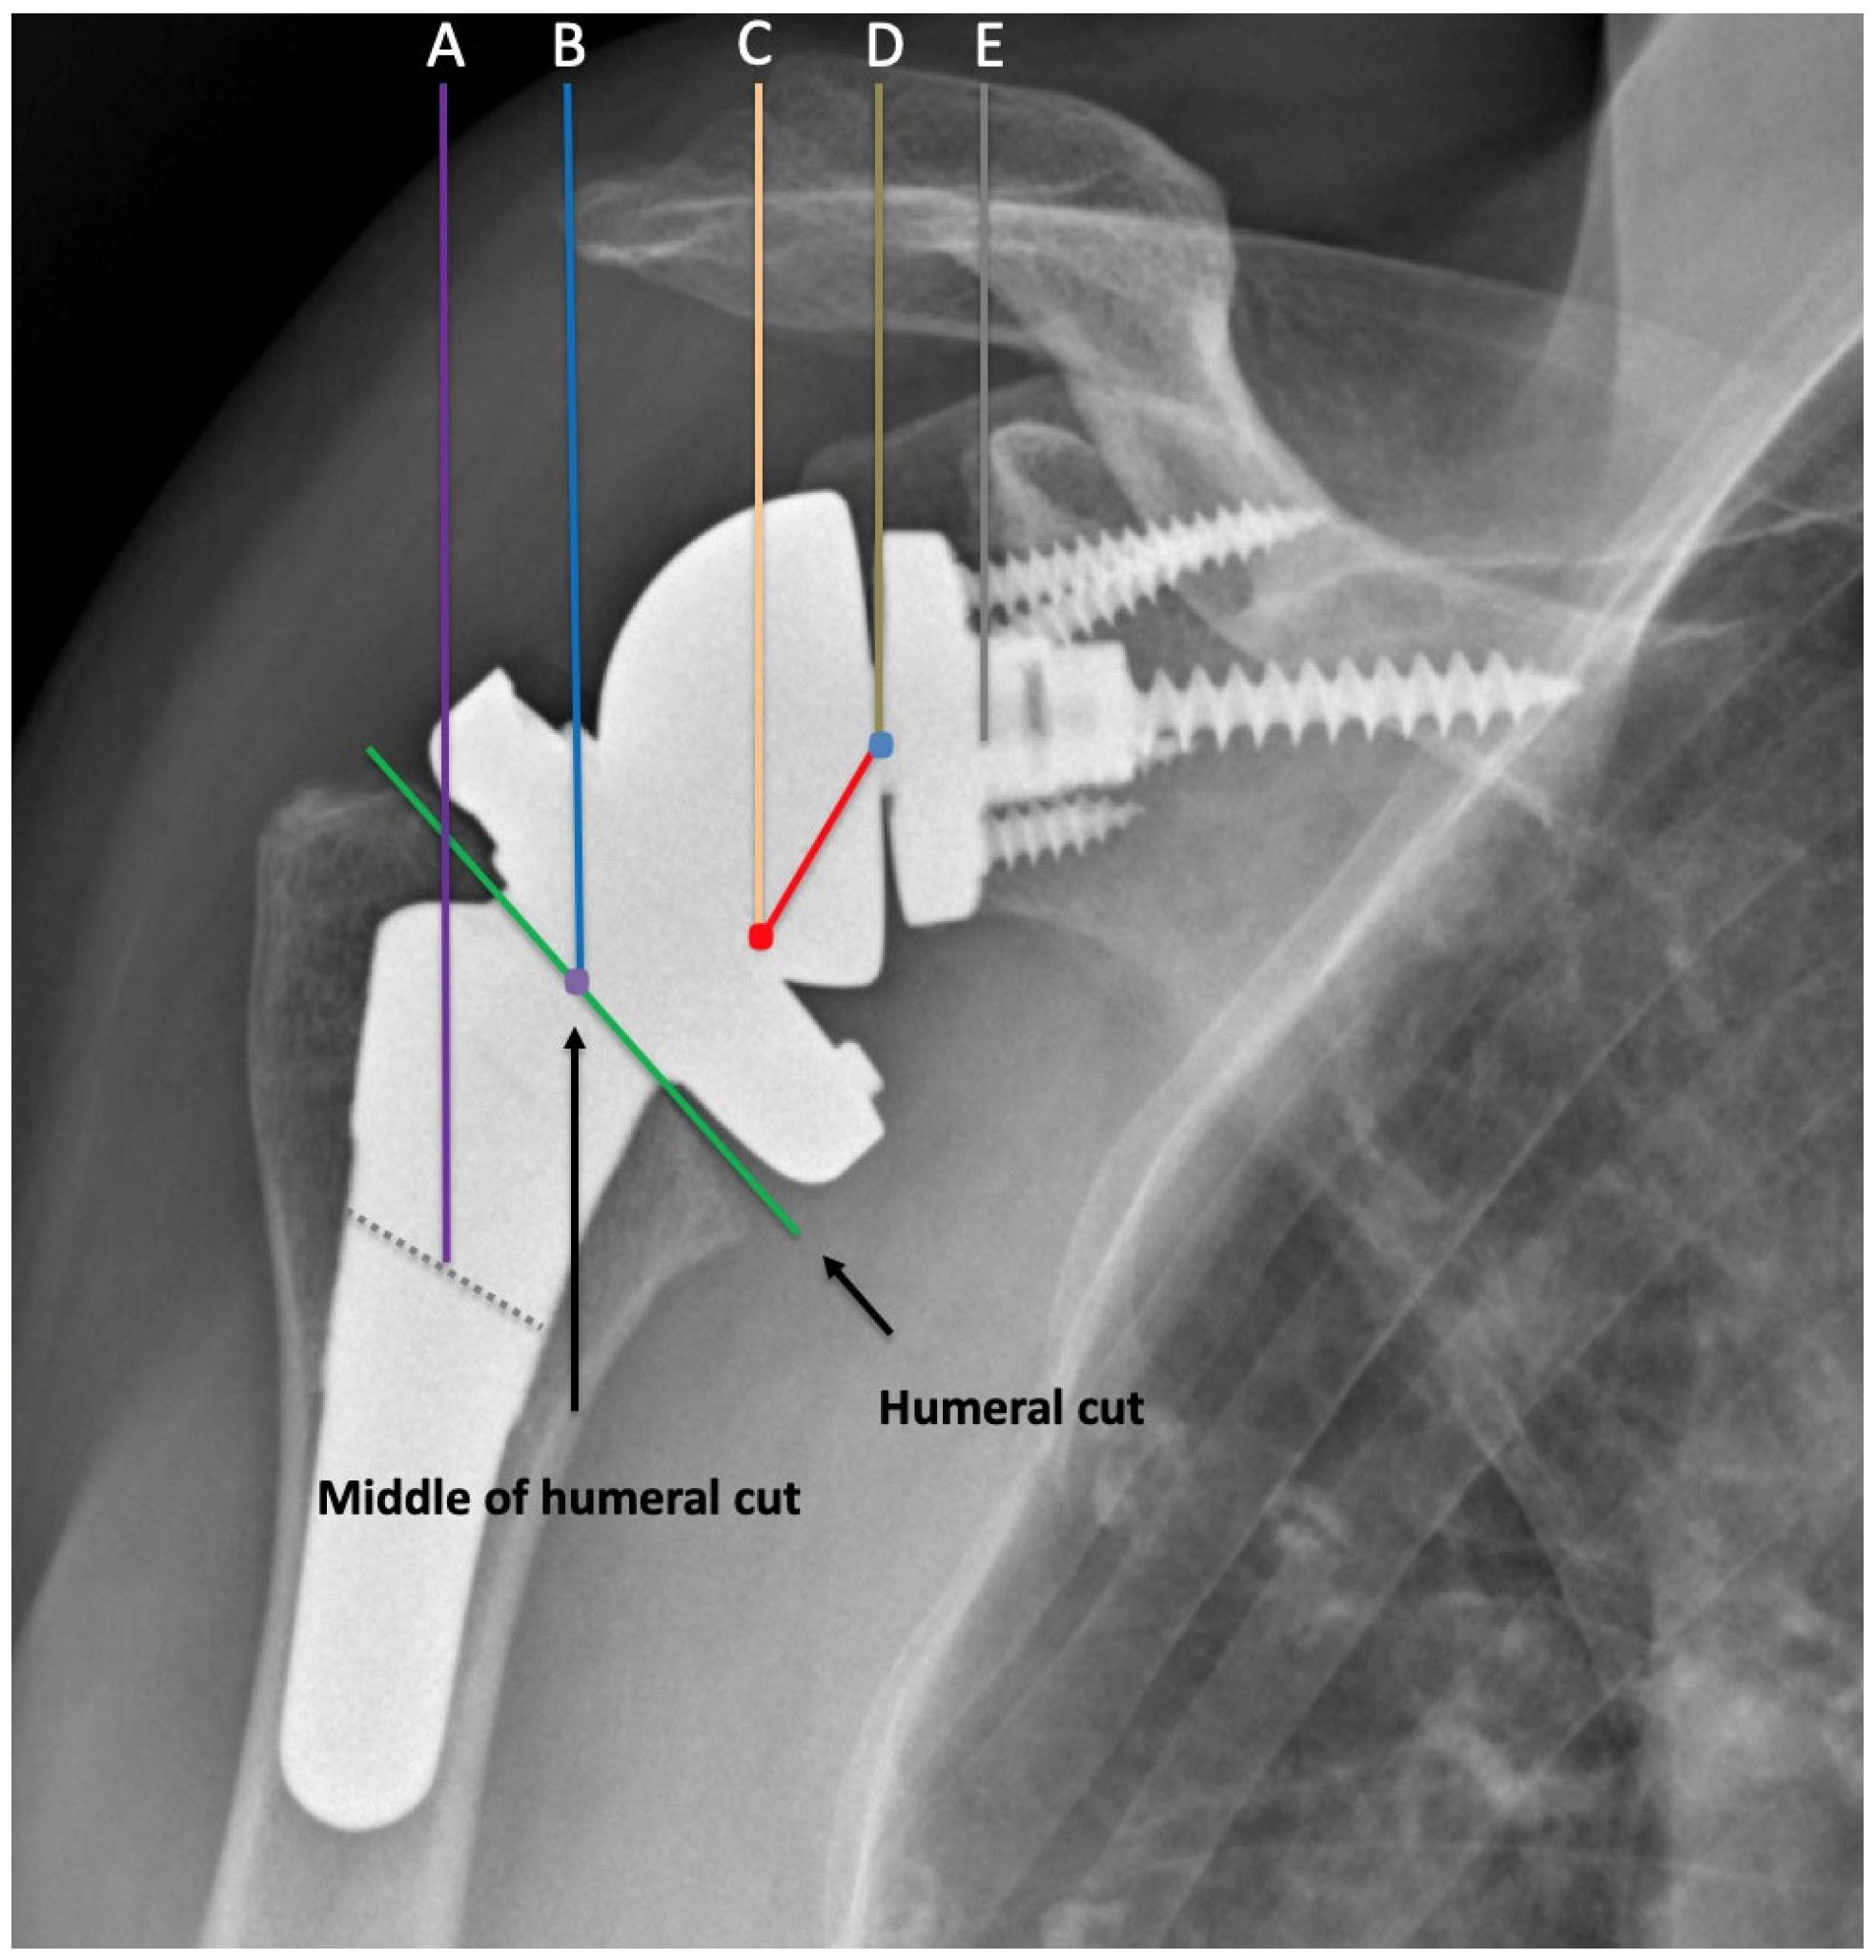

4. Radiographic Evaluation of Grammont-Style Reverse Arthroplasty

5. Radiographic Features of Lateralized Reverse Arthroplasty